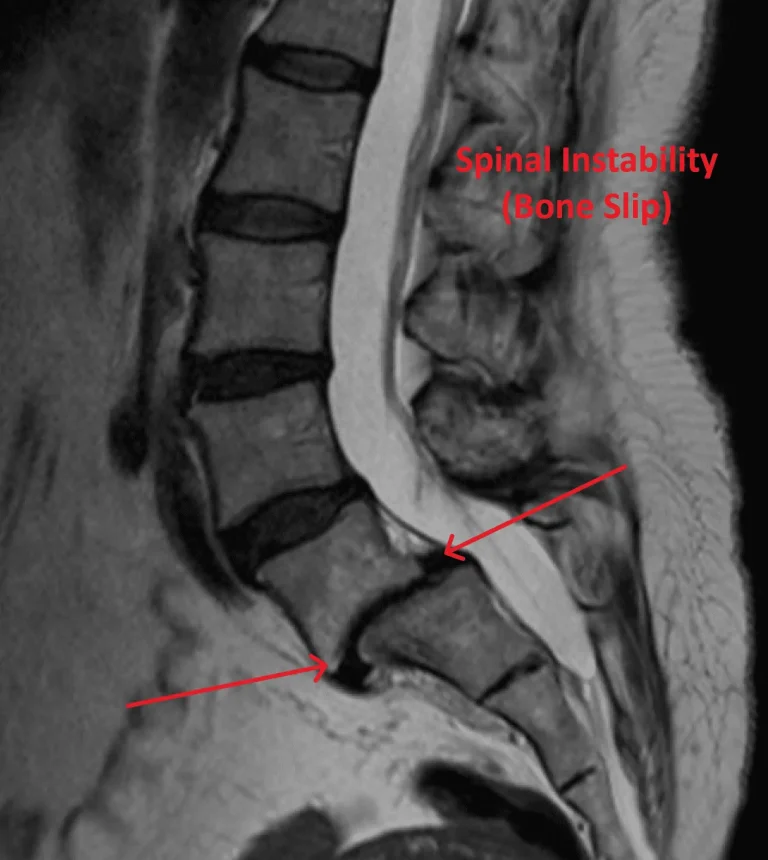

MRI scan showing spinal instability with bone slip, highlighted by arrows and labeled in red text.

Spinal Instability

Spinal instability and degeneration at levels above and below the implant.